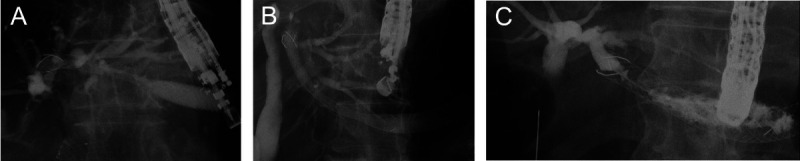

Background and objectives: Hyperplasia at the distal side of an EUS-guided hepaticogastrostomy (HGS) stent is one of the most frequent causes of stent dysfunction. However, risk factors for hyperplasia during EUS-HGS remain unclear. The aim of the present study was to determine the most appropriate stent site during EUS-HGS to obtain prolonged stent patency.

Method: This study included 100 consecutive patients who underwent successful EUS-HGS using a partially covered, self-expandable, metal stent (PCSEMS) between January 2017 and September 2022. The patients were divided into 2 groups according to the distal site of the PCSEMS at the intrahepatic bile duct, the peripheral side group and the central side group.

Results: There were 30 patients in the peripheral side group and 70 in the central side group. The diameter of the intrahepatic bile duct at the PCSEMS deployment site was significantly greater in the central side group (mean 7.90 mm) than in the peripheral side group (mean 4.25 mm; P < 0.05). Stent patency was significantly longer in the central side group than in the peripheral side group (median, 60 days vs. 144 days, P = 0.011), although overall survival was not significantly different. Hyperplasia was significantly more frequent in the peripheral side group. On multivariate analysis, the site of the PCSEMS (peripheral) was the only risk factor for stent dysfunction.

Conclusions: In conclusion, the distal site of the PCSEMS deployed at the hepatic hilar site from the confluence between B2 and B3 might play a role in obtaining longer stent patency.